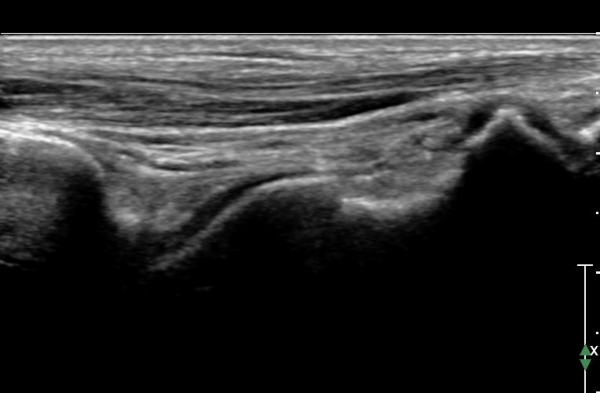

ÃÊÀ½ÆÄ °Ë»ç :  ¹ß¸ñ ¾ÕÂÊ Á¾´Ü¸é°Ë»ç¿¡¼­ ƯÀÌ ¼Ò°ß º¸ÀÌÁö ¾Ê´Â´Ù(»çÁø 1)